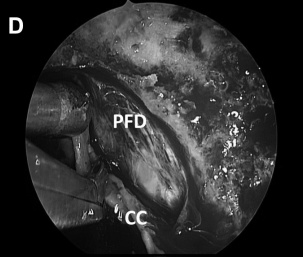

▼解剖、剥离并切除肿瘤包膜(D、E)

▼(L)使用鼻中隔瓣 (NSF)完成封闭。CC,囊包膜;PFD,后颅窝硬脑膜;S,蝶鞍;T,肿瘤。